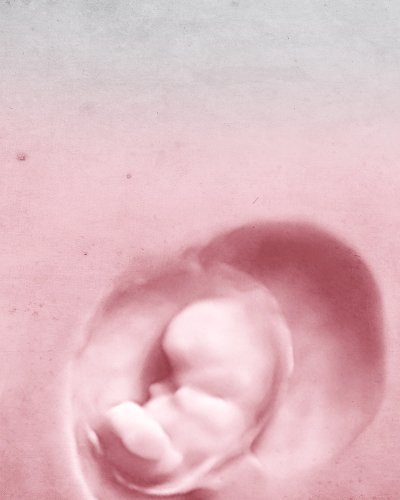

FORSCHUNG SCHENKT UNS LEBEN

Wir helfen Ihnen, eine Familie zu gründen